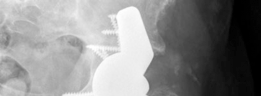

With less than 50% host bone contact, a hemispherical cup alone will fail to achieve biologic fixation. These massive defects require structural support spanning from the ilium to the ischium. A cup-cage construct is a highly effective solution.

First, a highly porous multi-hole cup is placed into the defect and secured with screws. Next, an ilioischial cage is contoured and placed over the cup, spanning the defect and fixed to the ilium and ischium. Finally, a polyethylene liner is cemented into the cage. This construct unloads the porous cup, allowing for biologic ingrowth while the cage provides immediate mechanical stability.

2. Cup Cage Constructs: As described above, spanning the discontinuity with a cage while utilizing a porous cup for ingrowth.